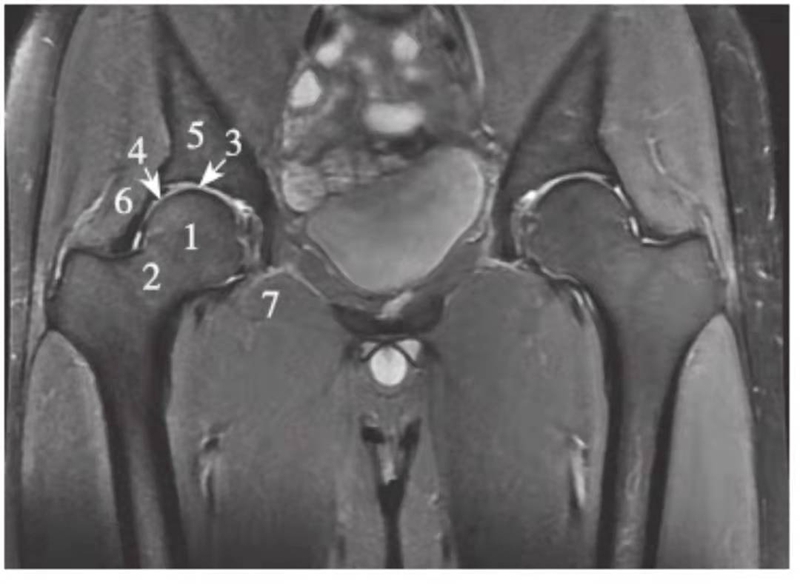

正常髋关节经股骨头中心层面PDWI抑脂像

1.股骨头;2.股骨颈;3.关节软骨;4.髋臼盂唇;5.髂骨;6.臀小肌;7.闭孔外肌

正常髋关节经股骨头后缘层面T1WI像

1.股骨头;2.大转子;3.髂骨;4.坐骨;5.闭孔内肌;6.闭孔外肌;7.臀小肌;8.臀中肌;9.臀大肌;10.内收肌群